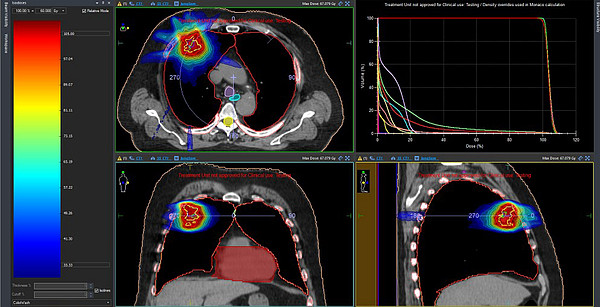

Стереотаксическая терапия представляет собой современный метод излечения рака, который позволяет точно направлять ионизирующее излучение на опухоль. Этот метод эффективно применяется для уничтожения раковых клеток в труднодоступных местах или в ситуациях, когда традиционная лучевая терапия может угрожать здоровью жизненно важных органов.

Решение о проведении стереотаксической терапии принимается на консилиуме врачей для выбора наилучшей стратегии лечения. Данный метод открывает новые горизонты в терапии сложных случаев онкологических заболеваний, где стандартная лучевая терапия может оказаться неэффективной или рискованной.